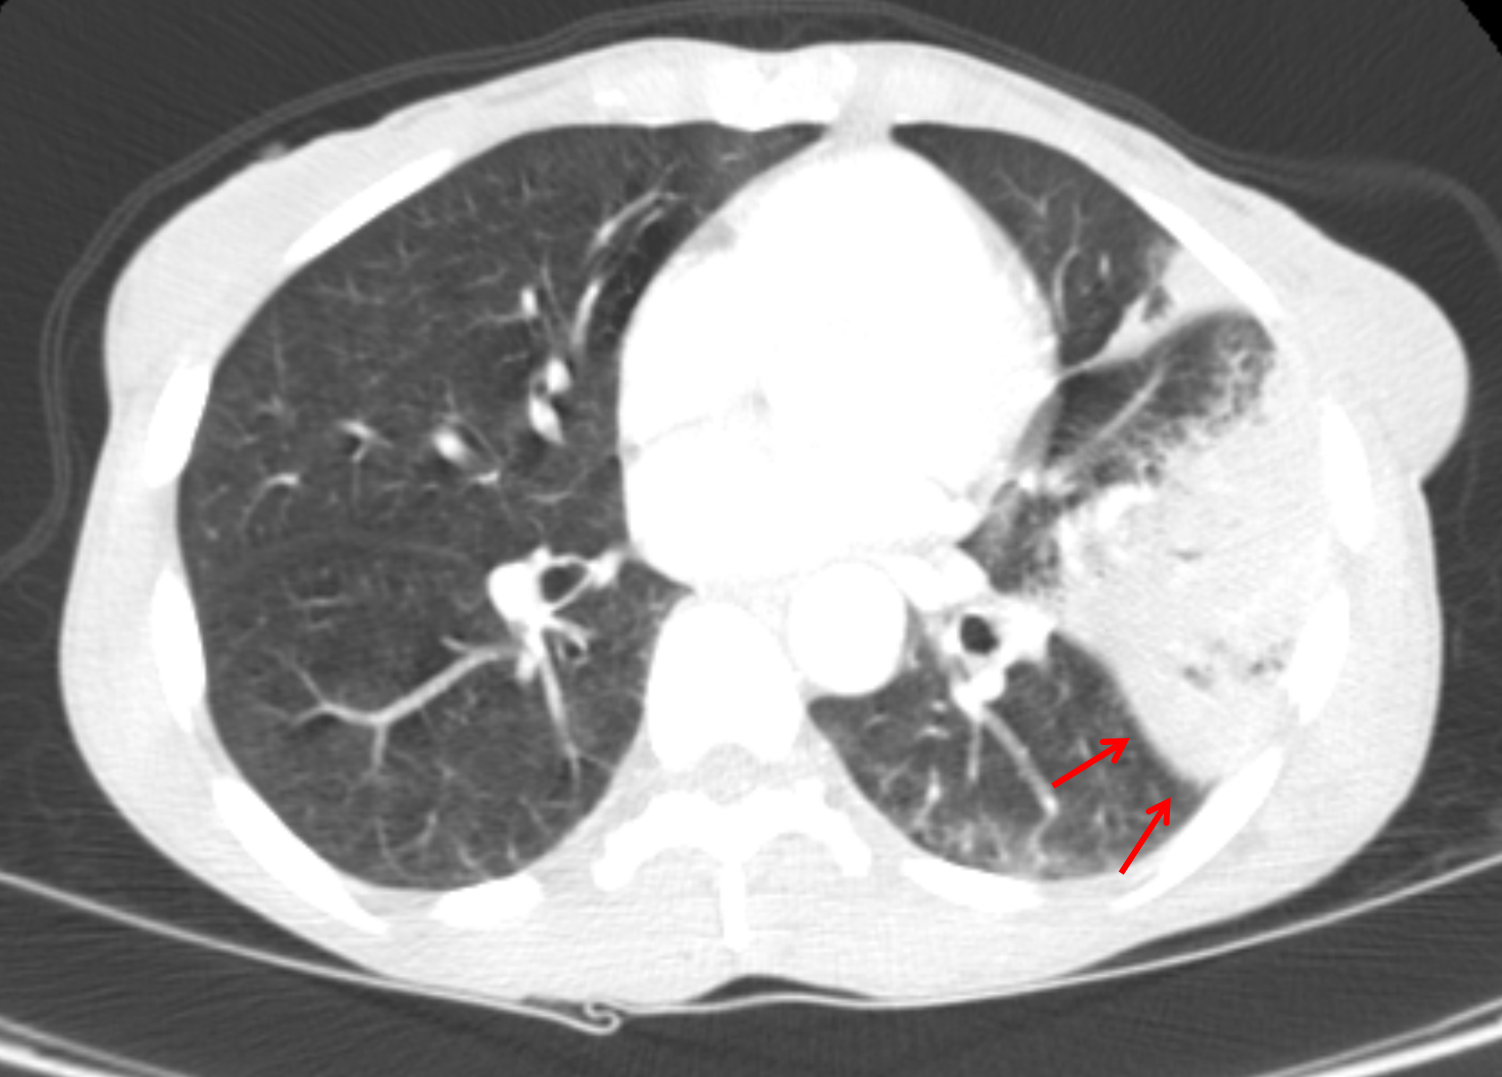

Age: 52

Sex: Female

Indication: Fever, chest pain

CT

Sample ReportLeft upper lobe pneumonia with associated bulging of the major fissure, which can be seen with aggressive infections, including Klebsiella pneumonia. No cavitation or pleural effusion.